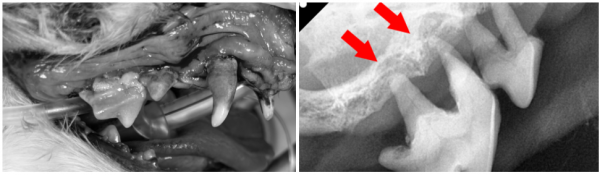

오히려 상태가 악화되어 눈 밑 피부가 터지고

고름이 배출되는 상황이 되어 내원하였습니다.

전반적으로 치아에 심한 치주염이 동반되어 있었으며,

이를 종합했을 때 치근단농양이 의심되었습니다.

→ 뭉이의 문제 치아를 발치하고,

피부에 난 농양 부위는 소독 후 봉합하였습니다.